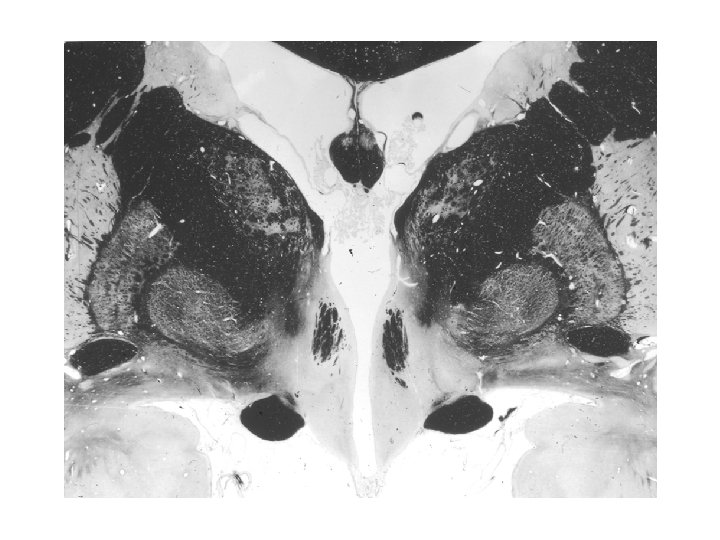

Nucleus arcuatus A hypothalamus magja a III. kamra alsó részének két oldalán, a retrochiasmaticus area és a corpus mamillare kezdete között, közvetlenül az eminentia medianától dorsolaterálisan. Sejtjeik számos neuropeptidet és peptid receptort, egy részük dopamint (A 12 catecholamin sejtcsoport) termel. Emberben nucleus infundibularisnak is nevezik. Neuronjai a hypothalamus más magjaihoz és a nyúltvelői és gerincvelői autonóm sejtekhez projíciálnak. A mag mediális részében nincs vér-agy gát. Jelentős szerepet visz a táplálékfelvétel idegrendszeri szabályozásában.

NEUROPEPTIDE Y (NPY) - NPY is the most potent orexigenic agent known - NPY neurons in the arcuate nucleus co-express Ag. RP - arcuate prepro. NPY m. RNA level is increased by food deprivation - arcuate NPY cells express leptin receptors (Ob-Rb form) - expression of NPY m. RNA in the arcuate nucleus is inhibited by leptin and insulin - the appetite-promoting effect of NPY is mediated by NPY Y 5 receptors - glucose, as well as carbohydrate-reach meal causes rapid increase in NPY level and NPY m. RNA expression in the arcuate nucleus - 2 -deoxy-glucose, which blocks glucose utilization stimulates the expression and production of NPY in the arcuate nucleus AGOUTI-RELATED PEPTIDE (Ag. RP) - Ag. RP-NPY neurons in the arcuate nucleus project to the paraventricular and dorsomedial nuclei, act on MCR 4 receptors to increase feeding - Ag. RP injections into the paraventricular nucleus result in a long-lasting food intake - leptin inhibits Ag. RP expression in arcuate neurons - Ag. RP blocks the inhibitory action of POMC on food intake - Ag. RP binds to MC 4 receptors and antagonize the action of α-MSH

PRO-OPIOMELANOCORTINS (POMC) - leptin stimulates POMC expression in the arcuate nucleus - POMC and leptin receptors are co-expressed in arcuate neurons - POMC is co-expressed with CART peptide - α-MSH released from arcuate POMC axons in the paraventricular nucleus exerts anorexic effects by acting on MC 4 receptors CART (cocaine- and amphetamine-regulated trascript) PEPTIDE - CART m. RNA expression is down-regulated in food-deprived rats - I. c. v. given CART inhibits food intake - CART peptide blocks the feeding response induced by NPY - CART cells in the arcuate nucleus express leptin receptors - CART expression in the arcuate nucleus is stimulated by leptin